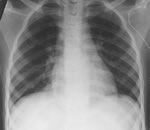

25.07.2013 г.МСКТ органов грудной полости с постобработкой данных в режиме МПР.Протокол исследования:в S3 правого лёгкого определяется мягкотканое объёмное образование вытянутой формы,с чёткими и гладкими контурами,размерами до 3,0х2,2х2,0 см.Несколько выше данного образования определяется зона неравномерного пневмосклероза, спаянная с паракостальной плеврой.Лёгочный рисунок не изменён.Корни лёгких структурны,не расширены. Просветы трахеи и крупных бронхов прослеживаются,не сужены.Средостение не смещено.Структуры средостения дифференцируются чётко.Дополнительных образований в средостении не определяется.Лимфатические узлы подмышечных областей,средостения,корней лёгких не увеличены.Жидкости в плевральных полостях нет.Костно-деструктивных изменений на уровне исследования нет.